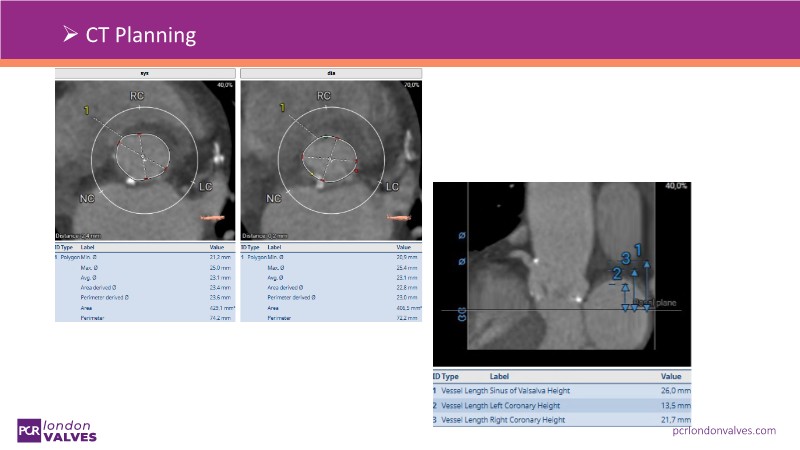

This session addresses emerging topics in structural heart disease by examining patient-centered solutions such as EVOQUE transcatheter tricuspid valve replacement (TTVR) and SAPIEN transcatheter heart valve-in-heart valve (THV-in-THV) procedures. It covers the latest data from Europe on redo TAVI, lifetime management strategies beginning with initial prosthesis planning, evolving patient selection for TTVR, and features an educational live case alongside expert panel discussions on procedure safety and efficacy.

- To understand the latest considerations and techniques for redo TAVI and get exposed to the latest data from Europe

- To learn how to maximise the benefits of TAVI with a lifetime management strategy that starts with the planning of the first prosthesis